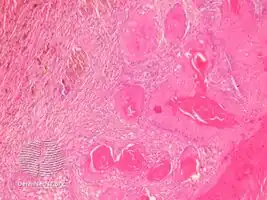

Proliferating trichilemmal cysts (also known as a "Pilar tumor", "Proliferating follicular cystic neoplasm", "Proliferating pilar tumor", and "Proliferating trichilemmal tumor"[2]) are a cutaneous condition characterized by proliferations of squamous cells forming scroll-like structures.[2][3]:678